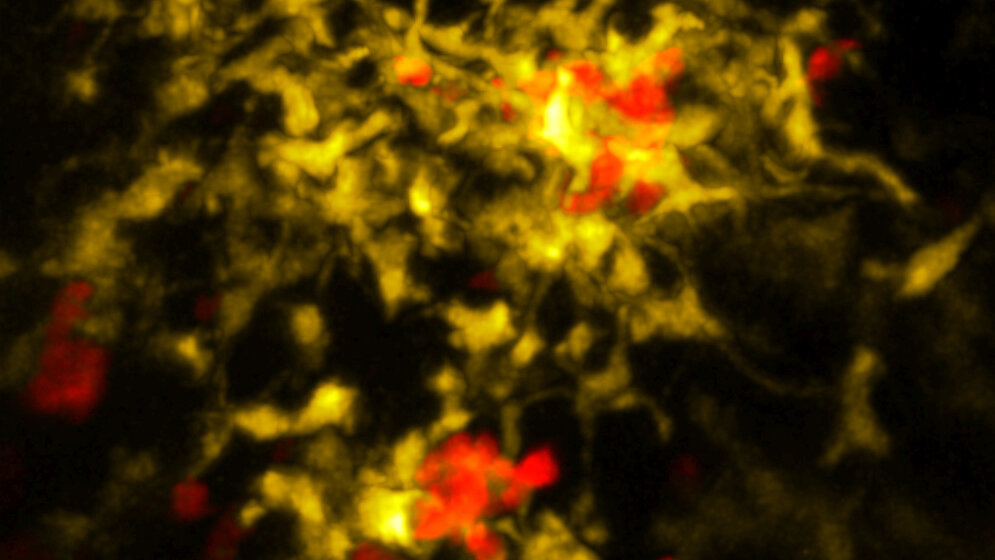

Direkt nach dem Kontakt mit dem Fremdstoff stößt die Killerzelle daher eine Art chemischen Hilferuf aus. Aufnahmen eines Spezial-Mikroskops zeigen erstmals, wie sich daraufhin bestimmte Spezialzellen der Körperabwehr zu ihr aufmachen. Nach ihrer Ankunft setzen diese Helfer verschiedene Immunprozesse in Gang. Erst dadurch wird die Killerzelle vollständig aktiviert.